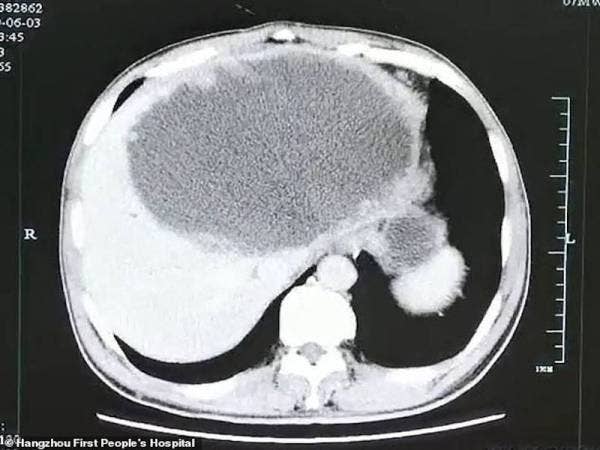

Telur cacing mencemari lalapan & salad? Menular dan membahayakan kesehatan Telur Cacing Pita Gerogoti Otak Seorang Anak, Kebiasaan Sepele dan Anggap Enteng ini Jadi Penyebabnya - Semua Halaman - Pop.Grid.ID GAMBAR TELUR CACING.docx Menelan Telur Cacing Pita Bisa Obati Autisme - Health Liputan6.com Gambar Telur Cacing Pada Tinja MACAM-MACAM TELUR CACING PARASIT - ANALIS SMK BANTUL MACAM-MACAM TELUR CACING PARASIT - ANALIS SMK BANTUL Cacing Tambang (Hook Worm) - Indonesian Medical Laboratory Telur Cacing Parasit Ini Dijual Sebagai Makanan, Berani Coba? Cacing Kremi - Gejala, Cara Menangani, dan Obat | HonestDocs Dr. Afiq Vet : “Gambar di bawah merupakan telur cacing yg berada dalam najis kucing. Telur ni akan menetas & berjangkit pada kucing lain pula. #MedTweetMY… https://t.co/WaUMnZn9hd” MACAM-MACAM TELUR CACING PARASIT - ANALIS SMK BANTUL gambar telur cacing.docx JSLM-396 TELUR CACING KOKON CACING LUMBRICUS RUBELLUS ,,.. | Shopee Indonesia MACAM-MACAM TELUR CACING PARASIT - ANALIS SMK BANTUL GAMBAR TELUR CACING - Shopaholic Medika | Facebook Pemeriksaan Telur cacing Gambar 5.1 Tiga tipe pembentukan telur cacing pita infeksi manusia. (a)… | Download Scientific Diagram MACAM-MACAM TELUR CACING PARASIT - ANALIS SMK BANTUL GAMBAR TELUR CACING Skema Siklus Hidup Cacing Perut Ascaris Lumbricoides - Salam Pikir Mengapa cacing tidak mati saat melewati lambung? - Quora Mengenal Telur Cacing Soil Transmitted Helminths | farinarizkyjiwasari 10 macam telur cacing.docx Pewarnaan parasit dan jamur NEMATODA. - Mulut terdiri atas tiga buah bibir. - Telur yang dibuahi berukuran + 60 x 45 mikron, berbentuk oval, berdinding - PDF Download Gratis Taenia saginata - Indonesian Medical Laboratory Gambar-gambar praktik Mengenal Caecilian, Hewan Amfibi Mirip Cacing yang Telurnya Seperti Kelereng - Global Liputan6.com MACAM-MACAM TELUR CACING PARASIT - ANALIS SMK BANTUL PEMERIKSAAN PARASIT CACING PADA DARAH – ALPONSIN Bayangkan otak anda di penuhi telur… - Public Health Malaysia | Facebook Telur Cacing Tanah (Kokon) Lumbricus Rubellus - YouTube Ada apa ya dengan telur cacing kremi ini (Enterobius vermicularis) - YouTube Telur cacing tanah (kokon) isi 250 pcs | Shopee Indonesia Gambar 1. Perubahan morfologi telur pada uterus cacing A. galli setelah… | Download Scientific Diagram PREVALENSI NEMATODIASIS SALURAN PENCERNAAN PADA SAPI BALI (Bos Sondaicus) DI KECAMATAN MAIWA KABUPATEN ENREKANG - PDF Free Download HELMINTHS (CACING) PADA KANAK-KANAK - BERSALIN BAB II TINJAUAN PUSTAKA 2.1 Infeksi Cacing Tambang Infeksi cacing tambang pada manusia terutama disebabkan oleh Ancylostoma duod MACAM-MACAM TELUR CACING PARASIT - ANALIS SMK BANTUL Cacingan pada Anak-Medicastore Pemeriksaan Parasit Pada Feses - Ilmu Ternak Mengenal Caecilian, Hewan Amfibi Mirip Cacing yang Telurnya Seperti Kelereng - Global Liputan6.com Hymenolepis nana - Indonesian Medical Laboratory Kesehatan Lingkungan: Parasit pada Air dan Tanah | L’Atelier de Joséphine Obat Cacing Kremi yang Ampuh Menyembuhkan Cacingan Taeniasis Dan Sistiserkosis Cacing Pita Taenia Solium ~ analiskesehatanATLM.com Telur cacing Strongyloides sp pada feses kambing | Seri Veteriner - YouTube INFESTASI TELUR CACING PARASITIK PADA TINJA KERBAU LUMPUR (Bubalus bubalis) ASEP SAEFULLAH - PDF Download Gratis Ratusan Telur Cacing Pita Ditemukan di Otak Bocah Ini, Kok Bisa? BAB II TINJAUAN PUSTAKA Penyakit Cacing Kremi - Gejala, Penyebab, dan Cara Mengobati | Halodoc.com 48308_PENELITIAN FESES Ascaris lumbricoides Cacing Tambang (Hook Worm) - Indonesian Medical Laboratory Telur Cacing Toxocara sp. - YouTube BAB II TINJAUAN PUSTAKA A. Nematoda Usus Nematoda usus merupakan kelompok yang sangat penting bagi masyarakat Indonesia karena Pemeriksaan telur cacing STH metode langsung | amaris satria http://repository.unimus.ac.id BAB II TINJAUAN PUSTAKA A. Ascaris Lumbricoides Ascariasis merupakan infeksi cacing yang paling s IDENTIFIKASI MORFOLOGI TELUR CACING DIAGNOSIS PENYAKIT KECACINGAN BERBASIS PENCITRAAN - PDF Free Download MACAM-MACAM TELUR CACING PARASIT - ANALIS SMK BANTUL Enterobiasis - Wikipedia bahasa Indonesia, ensiklopedia bebas Kesehatan Lingkungan: Parasit pada Air dan Tanah | L’Atelier de Joséphine Telur Cacing Pita Bersarang di Otak Seroang Anak, Kebiasan Sepele ini Bisa Jadi Pemicunya - Semua Halaman - Grid.ID Macam-macam telur cacing disertai… - Laboratorium Mikrobiologi | Facebook Telur cacing ‘bersarang’ dalam hati akibat makan ikan mentah Ascaris lumbricoides (Cacing Gelang) - Indonesian Medical Laboratory Laporan Praktikum Pemeriksaan telur cacing metode fluotasi - Yazhid Blog IDENTIFIKASI TELUR CACING PARASIT PADA FESES SAPI (Bos sp.) YANG DIGEMBALAKAN DI SEKITAR TEMPAT PEMBUANGAN AKHIR SAMPAH (TPAS) TAMANGAPA MAKASSAR - PDF Free Download majalahinfovet.com : Kenali dan Hindari Cacing Lambung Haemonchus Contortus pada manusia: 1. Gambar jenis-jenis telur cacing Ga Nyangka! Ini 9 Bentuk Telur Hewan yang Jarang Diketahui Oleh Nurhalina, SKM, M.Epid - ppt download Pola Defekasi dan Kajian Jenis Telur Cacing pada Tinja Landak Jawa (Hystrix javanica) Trichuriasis - ANAK FK Cacing Tambang (Hookworm) | hmkuliah Jangkitan cacing | Harian Metro Berniat Budidaya Cacing Tanah? Wajib Ketahui Hal-hal Berikut Ini! Infestasi Telur Cacing Parasitik pada Tinja Kerbau Lumpur (Bubalus bubalis) Toksokariasis - Wikipedia bahasa Indonesia, ensiklopedia bebas Trichuriasis - ANAK FK Internasional | Ngeri, Mata Seorang Pria jadi Sarang Ribuan Telur Cacing Pita Hymenolepis diminuta - Indonesian Medical Laboratory Kunci jawaban UAP parasitologi Prevalensi Nematoda Gastrointestinal pada Sapi Bali yang Dipelihara Peternak di Desa Sobangan, Mengwi, Badung 83+ Gambar Telur Cacing Pada Feses HD - Gambar Pixabay IDENTIFIKASI Toxocara canis PADA ANAK ANJING DI MAKASSAR PET CLINIC PROGRAM STUDI KEDOKTERAN HEWAN FAKULTAS KEDOKTERAN UNIVERSIT Hookworm, Ancylostoma duodenale, Necator americanus | Hidup Indah Bersama Rasulullah TweetSains Kacah on Twitter: “Jawapan untuk soalan penetasan telur cacing: kebanyakan telur cacing kelihatan sama di bawah mikroskop. Namun kesan jangkitan tidak sama. Ada ubat cacing yang tidak berkesan untuk sesetengah Benarkah Lintah dalam Kangkung yang Termakan Bisa Bersemayam di Usus? meTube.id - gadis kecil menelan telur cacing kremi karena suka gigit kuku - Tomonews Identifikasi Telur Cacing Pada Feses Anjing Telur Fasciola Hepatica (Cacing Daun)… - Laboratorium Mikrobiologi | Facebook Dokter Temukan 30 Telur dan Larva Cacing Pita di Dalam Otak Seorang Pria China - Halaman 2 - Tribun Wow Parasitologi Ialah ilmu yg mempelajari parasit dgn segala pengaruh-pengaruhnya di dlm tbh manusia Parasit m.hidup (organisme) yg mknnya, perumahannya. - ppt download Capillariasis Obat Cacing dan Tipe Parasit di Usus yang Harus Anda Tahu 5 Makhluk Mengerikan Ini Bisa Jadi Parasit di Tubuh Anda - Global Liputan6.com Optimasi Air Perasan Buah Merah (pandanus sp.) Pada Pemeriksaan Telur Cacing IDENTIFIKASI TELUR CACING ZOONOTIK PADA FESES Rattus tanezumi DI PASAR KOTA BANJARNEGARA IDENTIFICATION OF ZOONOTIC HELMINTH EGG